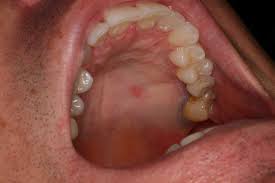

Allergic Reaction Bumps On Roof Of Mouth. STDs like Herpes and HIV infection. A bump on roof of mouth or palate can either be cancerous or non-cancerous. It could be allergies. If it is many bumps then it is an allergic reaction.

Roof of mouth pain questionnaire Use our free symptom checker to find out whats causing your pain. Pain can also happen from irritants like dental trauma smoking or eating certain foods. Signs of an allergic reaction often are present in the mouth and tongue and also can even reach the throat. If it is one bump in the same place you probably have a block salivary gland yes they are all over your mouth–even the roof of the mouth. Roof of mouth pain questionnaire Use our free symptom checker to find out whats causing your pain. While you could simply stop eating bananas and be safe it is best to have any severe food reaction properly diagnosed in this case i.